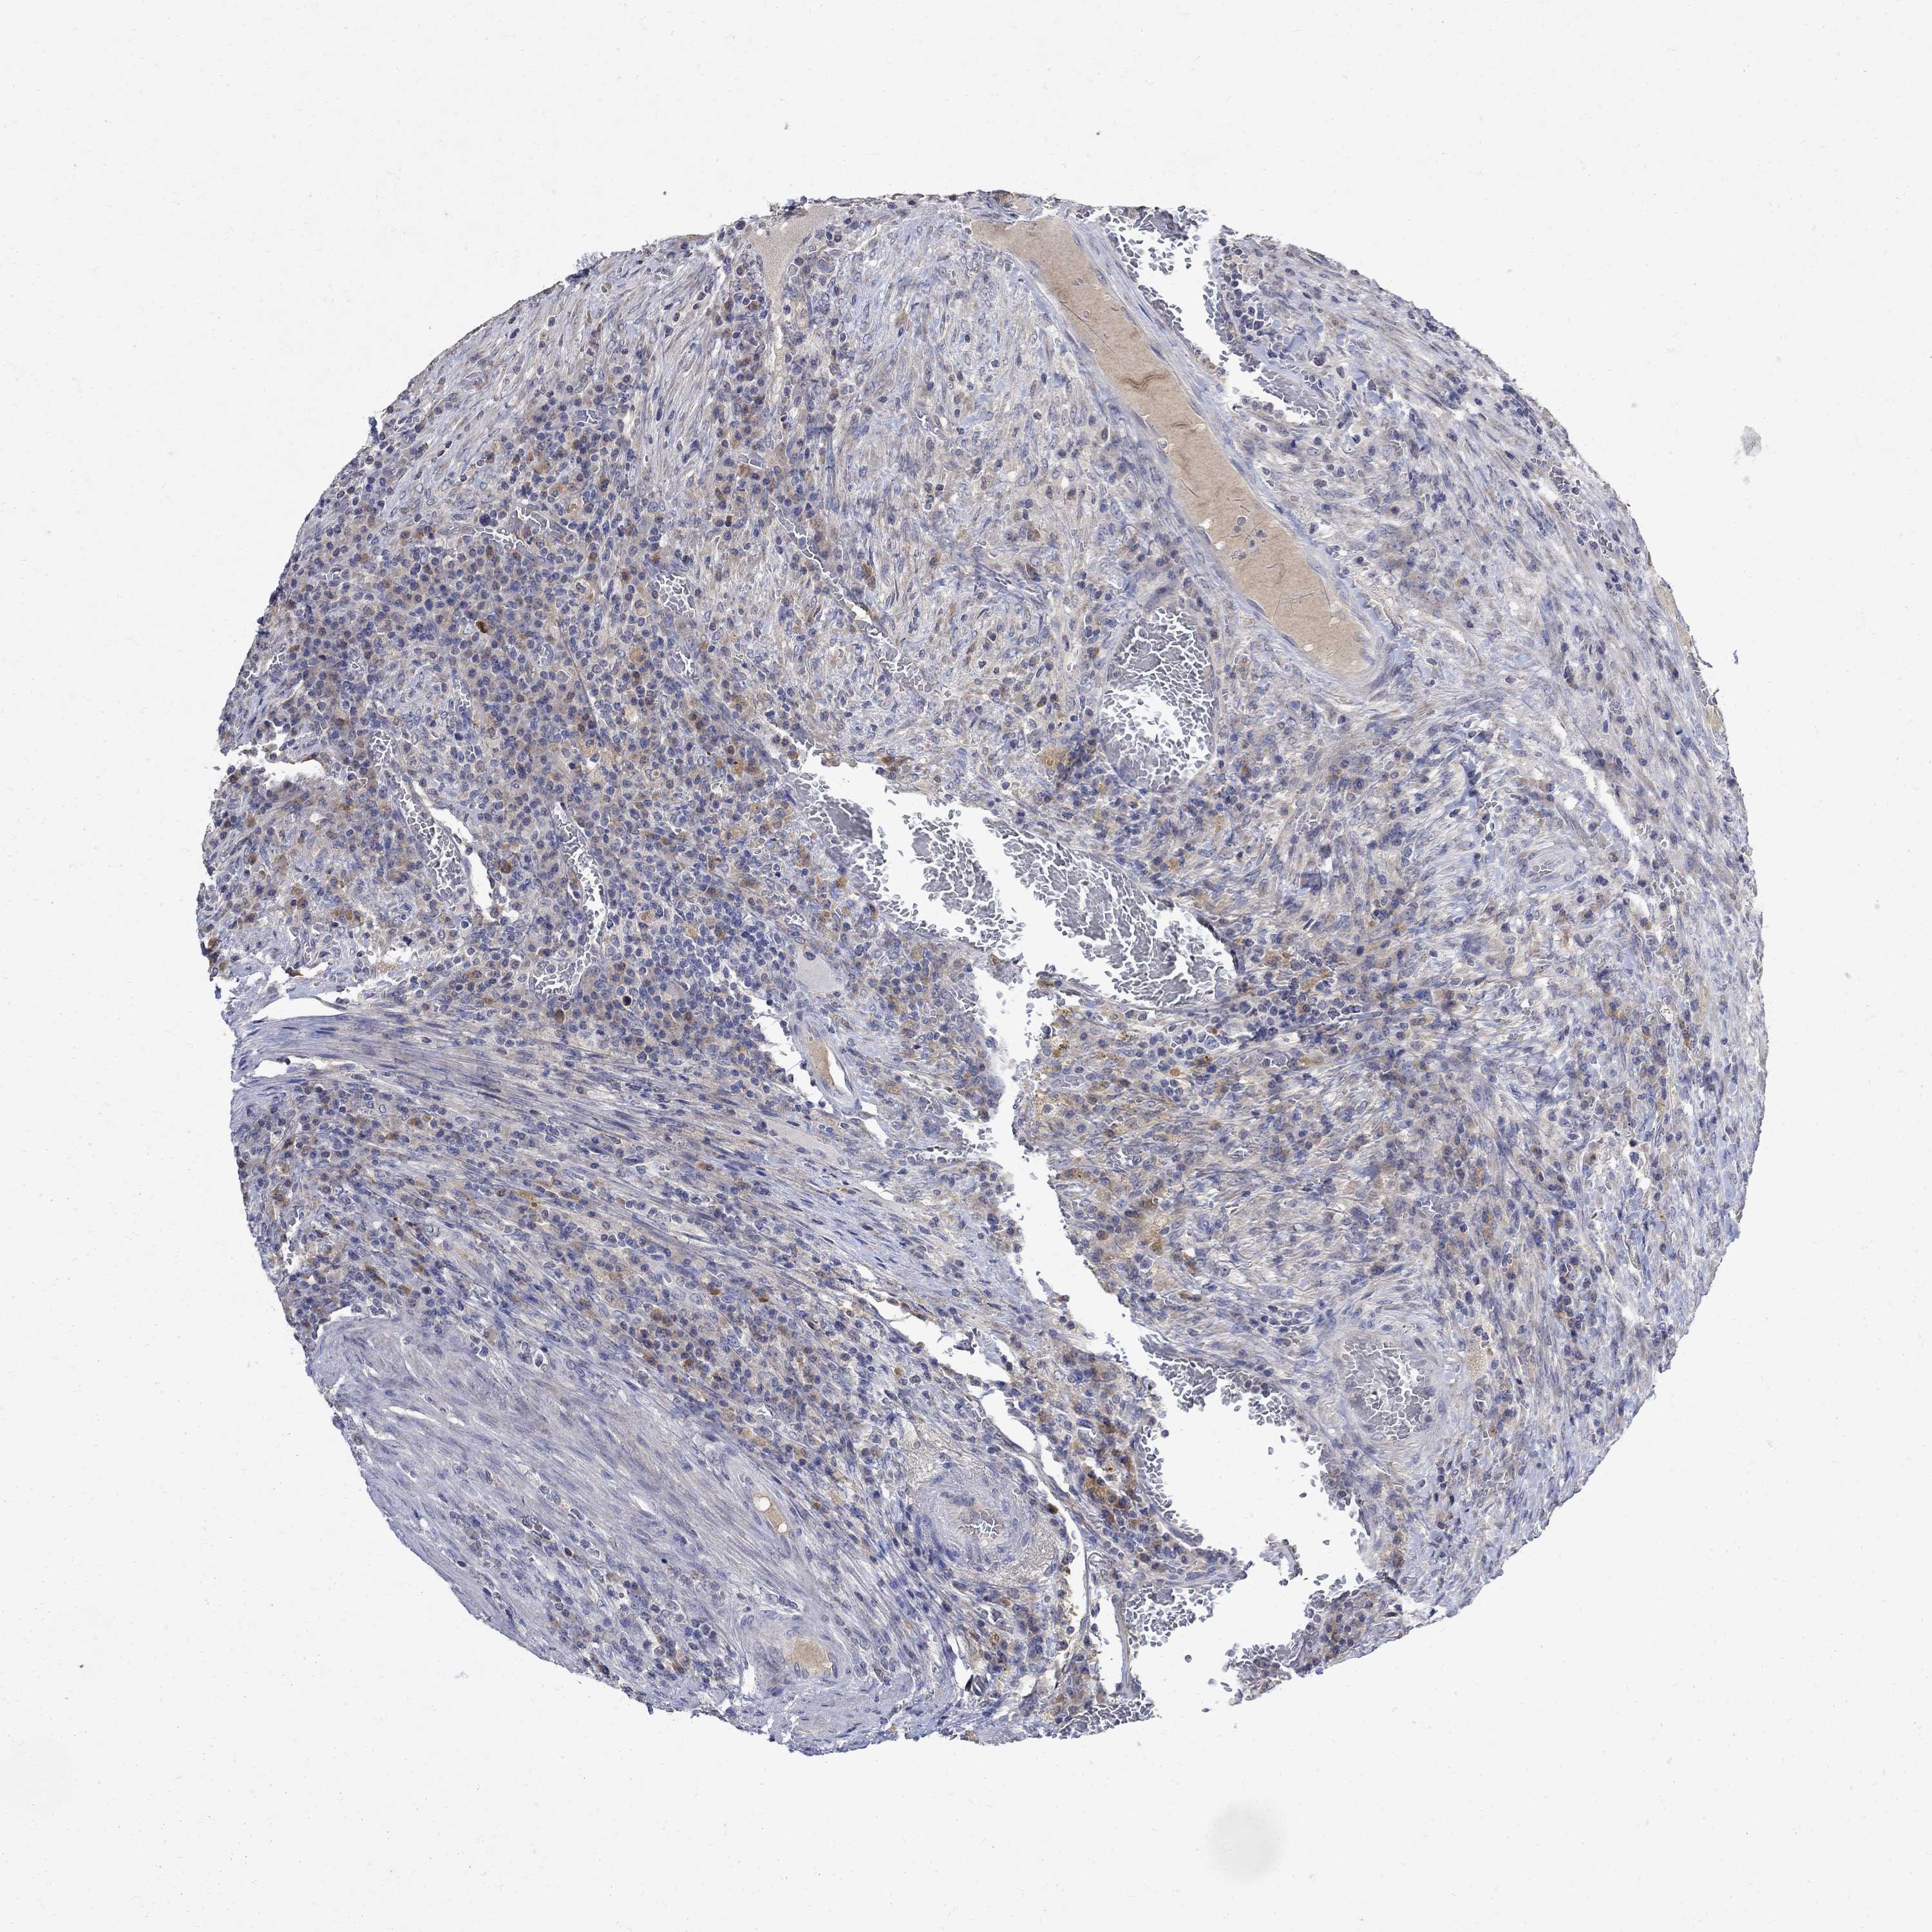

CANCER COLORECTAL CANCER Show tissue menu

Colorectal cancer

Colon adenocarcinoma